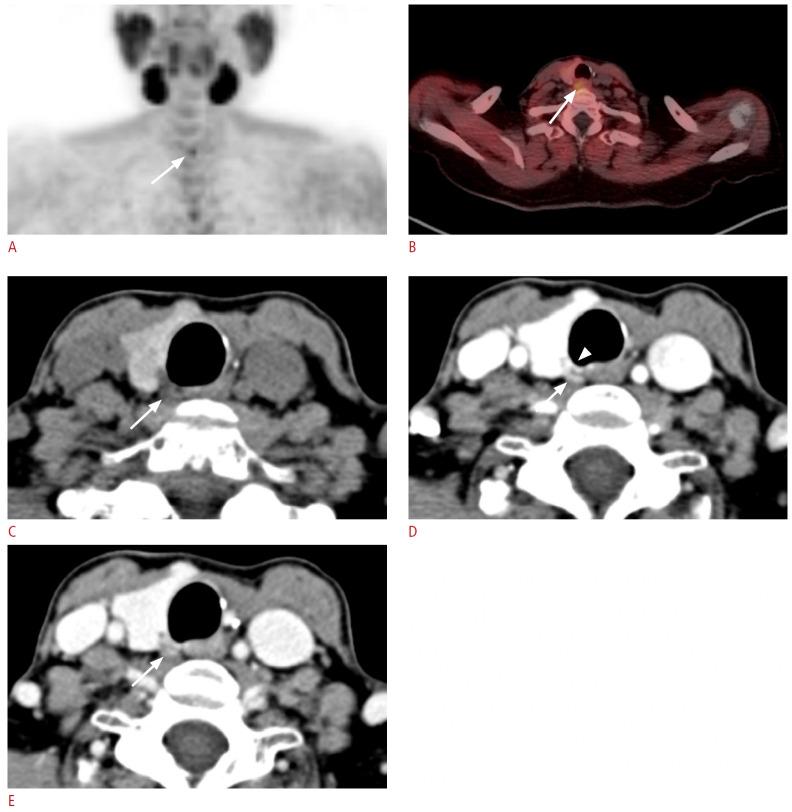

The parathyroid glands play a key role in maintaining calcium-phosphate homeostasis by secreting parathyroid hormone (PTH). Hyperparathyroidism, characterized by the inappropriate overproduction of PTH, is classified as primary, secondary, or tertiary according to its pathophysiology. Although diagnosis is principally biochemical, imaging is essential for accurately localizing hyperfunctioning glands. Precise localization allows for focused minimally invasive surgery, reduces the risk of persistent or recurrent disease, and avoids unnecessary bilateral neck exploration. Current techniques include high-resolution ultrasonography, 99mTc-sestamibi scintigraphy with single-photon emission computed tomography/computed tomography (CT), four-dimensional CT, magnetic resonance imaging, and positron emission tomography/CT with tracers such as 18F-fluorocholine. Parathyroidectomy remains the mainstay of treatment; however, recent advances in thermal ablation have expanded treatment options for patients unsuitable for surgery.

甲状旁腺通过分泌甲状旁腺激素(PTH)在维持钙磷稳态中起关键作用。甲状旁腺功能亢进症的特征是PTH分泌过多,根据其病理生理学可分为原发性、继发性或三发性。虽然诊断主要依靠生化检查,但影像学检查对于准确定位功能亢进的腺体至关重要。精确的定位有助于进行有针对性的微创手术,降低持续性或复发性疾病的风险,并避免不必要的双侧颈部探查。目前的技术包括高分辨率超声检查、99mTc-甲氧基异丁基异腈闪烁显像联合单光子发射计算机断层扫描/计算机断层扫描(CT)、四维CT、磁共振成像以及使用18F-氟胆碱等示踪剂的正电子发射断层扫描/CT。甲状旁腺切除术仍然是主要的治疗方法;然而,热消融技术的最新进展为不适合手术的患者扩展了治疗选择。